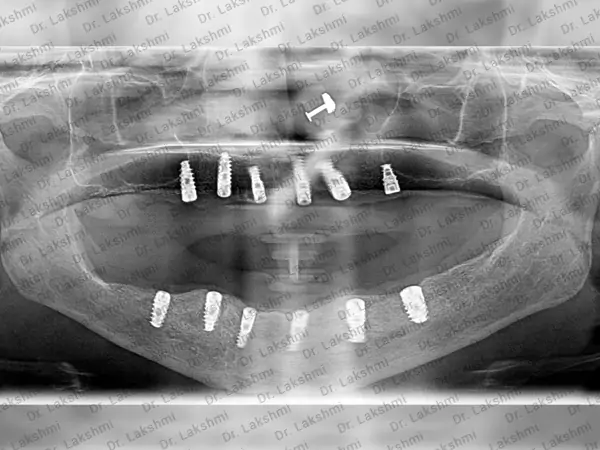

X-Ray Image

The all on 6 dental implant is generally used for patients who have a limited bone tissue in the mandible. Dental implants are generally used as a replacement for individual teeth. Whereas, all on 6 implant procedures rely on six dental implants that keep dentures firmly fixed to a place. The all on 6 dental implant procedure is used as a replacement for the entire upper or lower set of teeth. The procedure uses six dental implants and creates a permanent prosthesis. This prosthesis acts as an anchor for a bridge or over-denture. The six implants are placed permanently in the lower or upper jawbone to permanently anchor prosthetic teeth in place. The implant that is placed in the jaw fuses with the jawbone with time and gives natural looking teeth.